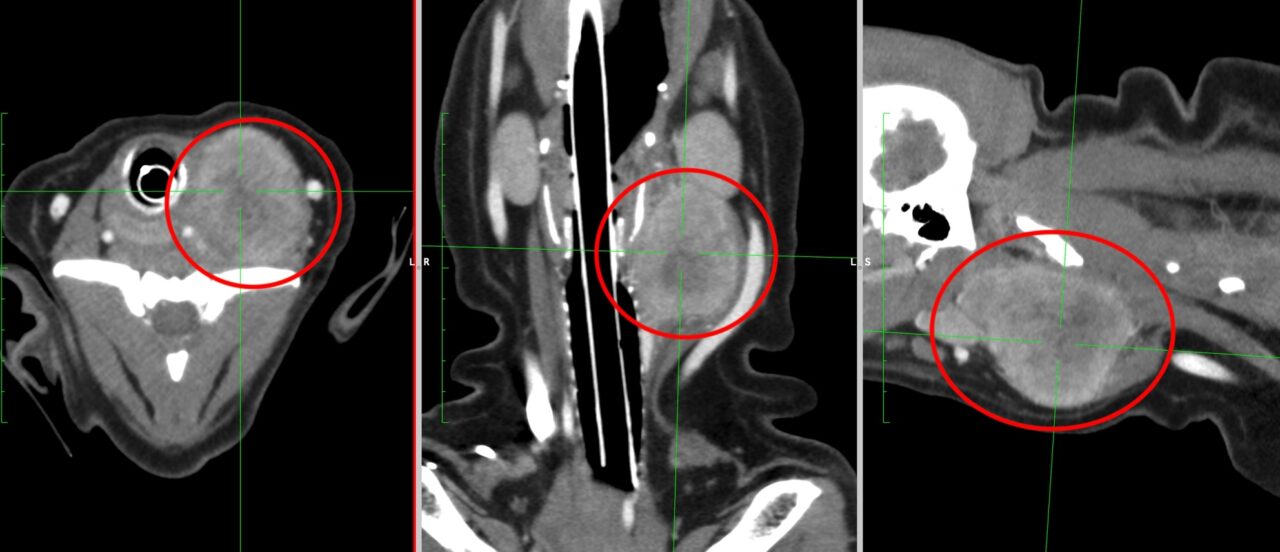

・CT検査:がんの大きさや広がり、リンパ節転移、遠隔転移の評価

※CT検査はより綿密な治療方針を決定するうえで必須の検査です

扁桃の扁平上皮癌がリンパ節転移したCT画像(赤丸)